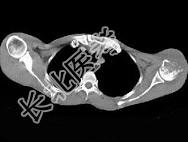

- 单项选择题男,29岁, 行走时不慎跌倒,曾拟为左肱骨头骨折并行固定, 但半年后疼痛未减轻,触压局部骨质松软, 如触及乒乓球感,明显叩击痛, 结合图像,最可能的诊断是 ( )